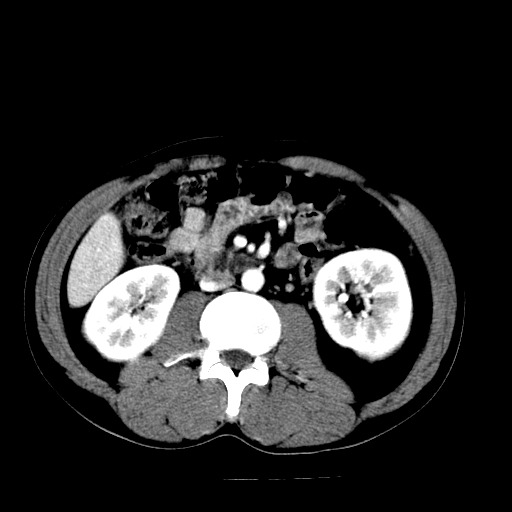

以下是引用天南地北在2007-4-30 13:36:00的发言:[br]支持慢性胰腺炎伴有假性囊肿

以下是引用andymaomao在2007-4-30 14:28:00的发言:[br]支持:1.慢性胰腺炎并假性囊肿形成可能;[br] 2.左肾形态稍增大,旋转不良。